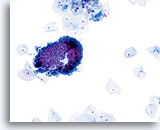

Postpartum

HSIL in a postpartum sample. Note the increased N/C ratio and abnormal chromatin in the HSIL cells as compared to the parabasal cells, apparent even at low magnification.

20X